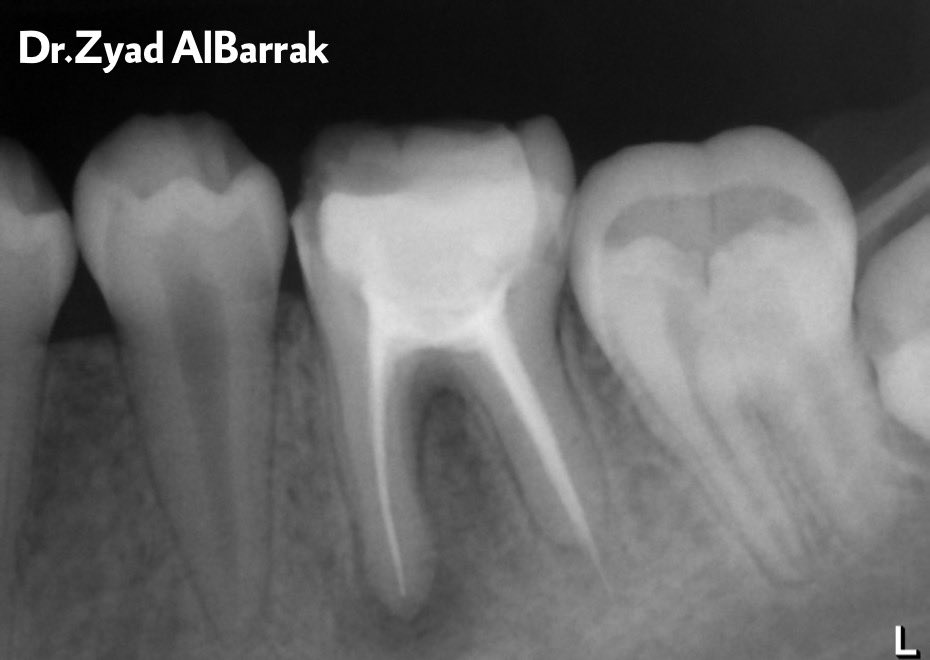

Tx procedure:

1st visit:

Remove all GP by profile ,(04- 30) file and chloroform to get access to all the canals.

Irrigate with NaOCL 5.25%, saline, CHX.